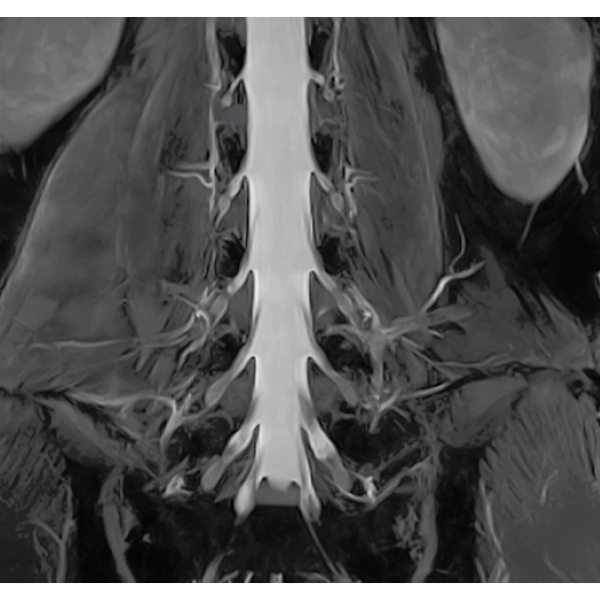

Imperfect imaging data to be better image quality through post-processing

By providing functions to remove and suppress artifacts in the imaging data and to generate reconstructed images from limited imaging data, it reduces the re-imaging rate and supports the realization of smooth MRI examinations.

Reduce artifacts caused by patient movement, such as coughing or sneezing, by post reconstruction.

Improving SNR and reducing wrap-around artifact through post reconstruction.

Even if the examination is interrupted, the minimum necessary data can be reconstructed later.

When motion artifacts occurs in the image due to coughing, sneezing, or involuntary movements, either or both the visual information acquired by monitoring cameras, Synergy Vision, and the intrabody information acquired by the navigator pulse can be used to provide an image with reduced artifacts. This reduces the re-imaging rate.

Body movements that affect image quality are detected from monitoring cameras based on thresholds derived for each body part.

Movements within the body are detected by navigator pulses. Body movements that significantly affect image quality are detected based on the error between pulses.